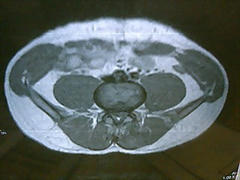

そして3ヶ月経過後の2006年7月。

身長 172cm / 体重 75.5kg

体脂肪率 21.6% / 筋肉率 32.9% / BMI 25.5

5キロ減って、体脂肪率やBMIを見ると合格ラインまであと一歩!!

・・・なんですが、MRIを見てみるとこんな感じ。

確かに筋肉がちょっと増え、お腹から背中までの厚みがちょっと薄くなってはいるようですが、依然として痛すぎます

数値に騙されてはいけません!!